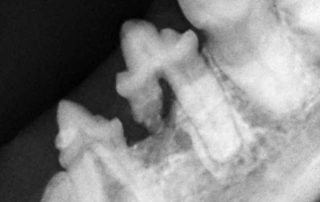

Werden die Zähne nicht täglich intensiv geputzt, bleibt ein Belag, die „Plaque“ zurück. In diese Schicht lagern sich nach und nach Mineralstoffe und Bakterien ein. So entsteht an den Außenflächen der Zähne harter, braungrauer Zahnstein. Durch die Eiter erregenden Keime in Plaque und Zahnstein entzündet sich das Zahnfleisch, es wird rot und riecht Übelkeit erregend. Schreitet die Zahnfleischentzündung (Gingivitis) weiter voran, verlieren die Zähne oft vollständig ihren Halt, bleiben aber als ständiger Entzündungsherd häufig noch jahrelang im Kiefer. Häufig entstehen, vielfach unterhalb des Zahnfleischsaumes, Löcher in den Zahnhälsen und Zahnwurzeln. Diese werden als FORL (feline odontoklastische resorptive Läsionen) bezeichnet; Die Zahnsubstanz löst sich regelrecht auf.

Zunächst ist die Entfernung des krank machenden Zahnsteins und die Wiederherstellung eines gesünderen Zahnfleisches wichtig. Da die Beläge auf den Zähnen mit einem Ultraschallgerät entfernt und die Zähne anschließend aufwändig poliert werden müssen, ist eine schonende altersangepasste Vollnarkose unumgänglich. Lockere und bereits angegriffene Zähne werden entfernt. Wegen der Eiterbakterien werden Antibiotika über eine bestimmte Zeit ebenso verabreicht wie wirkungsvolle Schmerzmedikamente.